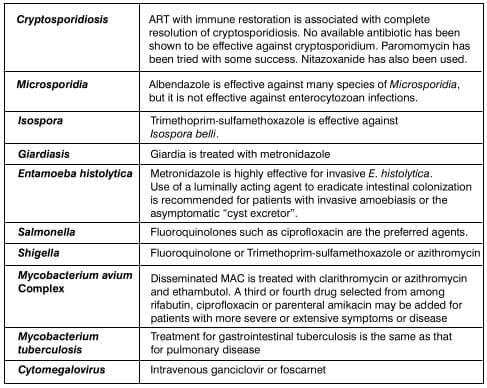

- Bacteria: Salmonella, Shigella, Campylobacter

- Parasitic infections: Cryptosporidium, Isospora, Giardia, Microsporidia, Entamoeba histolytica

- Mycobacterial infections: Mycobacterium avium complex (MAC), Mycobacterium tuberculosis

- Viral infections: Cytomegalovirus

- Drug-associated diarrhoea: Certain antiretrovirals such as protease inhibitors (e.g. nelfinavir)

commonly cause diarrhoea

- Idiopathic diarrhoea, often labelled 'HIV enteropathy'

Diarrhoea results from either small intestinal or colonic pathologic conditions. A careful history and physical

examination will direct the evaluation and treatment strategy of AIDS-associated diarrhoea.

Small-intestinal disease produces large volume diarrhoea that is frequently associated with dehydration and serum

electrolyte abnormalities. Abdominal pain, gaseous distension, nausea and vomiting also may be present. Tenesmus

and fecal leukocytes are absent.

Colonic diarrhoea is less voluminous, and dehydration is uncommon. Tenesmus and left lower quadrant pain are

common.

Bacterial infections

Salmonella, Shigella and Campylobacter cause more severe diarrhoea with longer duration of

illness in the immunocompromised host. The diagnosis is established through cultures of stool and blood.

Endoscopy may be useful.

Parasitic infections

Cryptosporidium, Isospora, Giardia and Microsporidia all infect the small intestine.

Entamoeba histolytica is uncommon but when present involves the caecum, ascending colon and terminal

ileum. Strongyloides stercoralis may also be encountered. The diagnosis can be established through

microscopic identification of oocytes in stool or tissue.

Viral Infections

Cytomegalovirus (CMV) is the most important viral cause of AIDS-associated diarrhoea. CMV may affect any part of

the Gl tract; colitis and oesophagitis are quite common.

Mycobacterial infections

Mycobacterium avium is found in macrophages in the lamina propria of the small intestine or colon.

Mycobacterium tuberculosis is most commonly found in the caecum and terminal ileum.